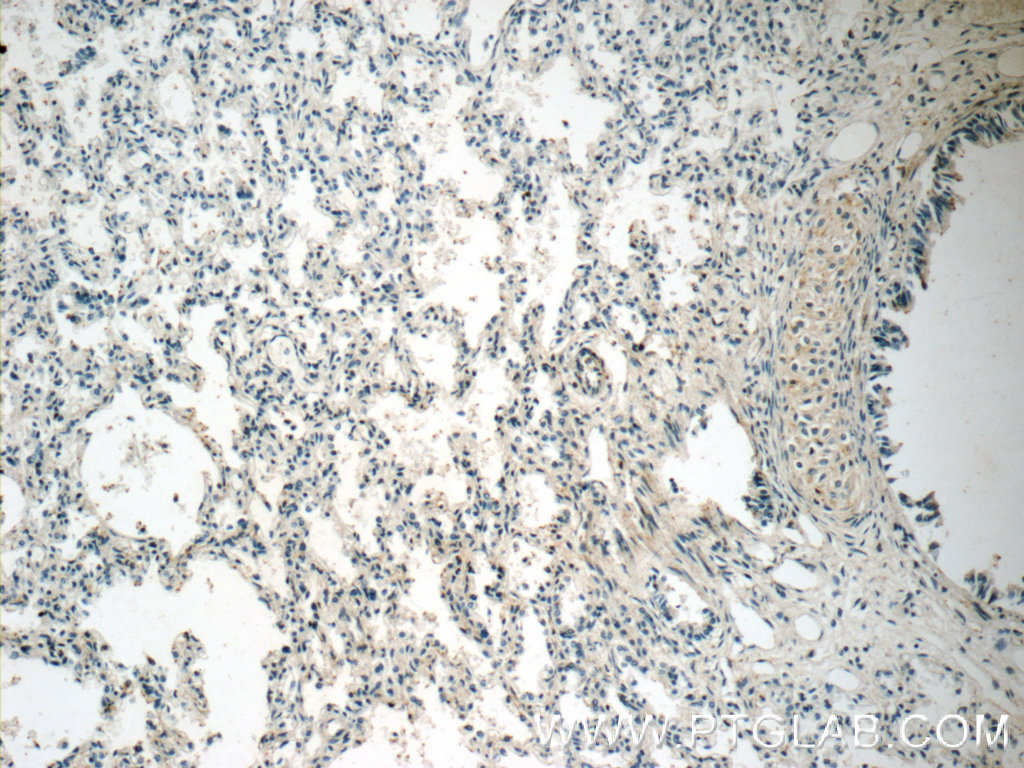

| Positive IHC detected in | human lung tissue |

| Recommended dilution | WB : 1:250-1:1000 IHC : 1:20-1:200 |